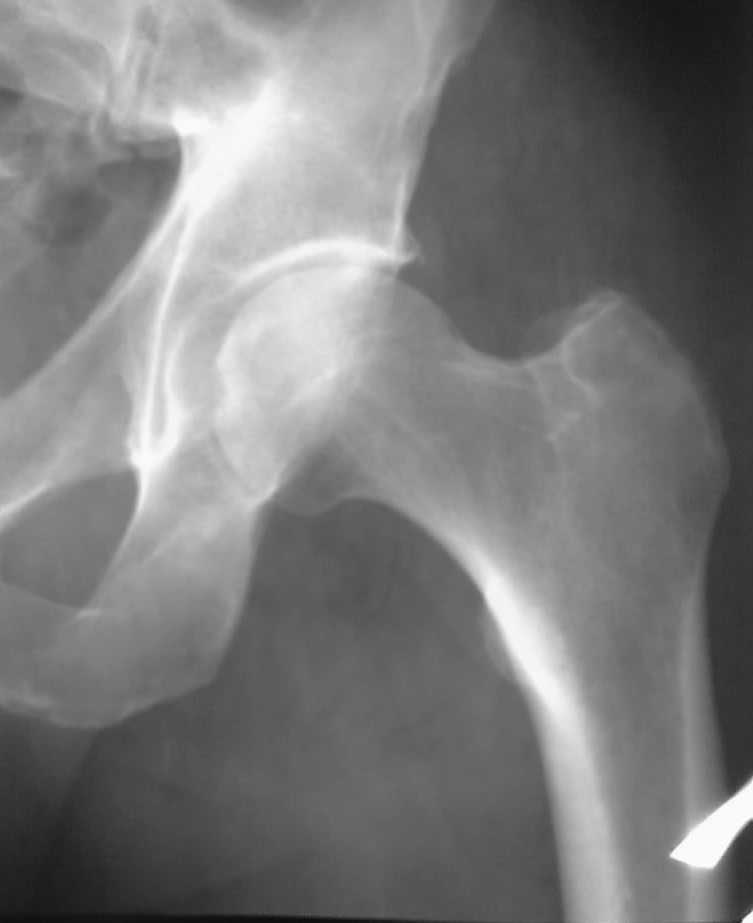

Что-то сегодня снимок не очень получился, но + аксиалка. Жалобы на появление боли в прав т.б. суставе без видимых причин, остро, диагноз при поступлении "Острый артрозо-артрит". Написал сужение суст. щели (?). Закл.: артроз 1? Рек-но МРТ. Мучают сомнения, действительно ли сужена суст щель (при измерении не менее 3 мм)?

Зри в корень!

"Ну, вы, блин, даете" (с) Издеваетесь, Владимир Борисович?! Выраженное сужение+субхондральный остеосклероз вертлужной впадины+периартикуллярное костеобразование; ситуацию спасает пока еще сохранная головка бедр. кости. Однозначно 2-я стадия, без вопросов

"Выраженное сужение" Не соглашусь. "субхондральный остеосклероз вертлужной впадины" Если, Андрей Юрьевич, вы о прямом снимке, так это дефект пересъемки с негатоскопа ("заплывание" светлых частей снимка). Убейте, периартикулярного костеобразования не нашел

Не, больше Косинской-1 не дам. 2-я только по Келлгрену и то с натяжкой.

В.Б. Серов << Мучают сомнения, действительно ли сужена суст щель (при измерении не менее 3 мм)? >> В норме рентгеновская суставная щель тазобедренного сустава взрослого мужчины = 6мм. А 3мм – это 50% I-II стадия (на границе), + хорошо выраженное обызвествление губовидного хряща, что ещё нужно? Классический ДОА.

Воля ваша, Владимир Борисович. Что ж мне, Вас переучивать, что ли? И не с руки, и не по чину. А свой вывод я сделал, именно по Вашему прекрасному аксиальному снимку. Прямой, и впрямь, не совсем удачный. А пишу я всегда по ранее утвержденной Косинской, без этих зарубежных штучек (кстати, Марио тоже пишет по классификациям своих американских, а не еропейских, ассоциаций).